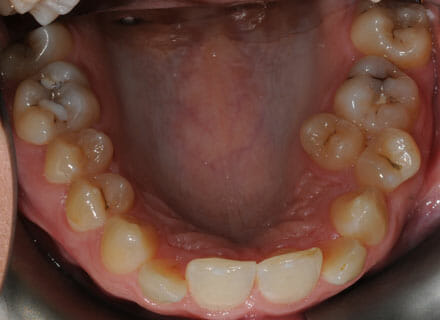

This lady came to us because she was unhappy with her crooked, uneven teeth.

The front ones were sticking out and she didn’t like her overbite. we were to move all the teeth sticking out back to where they should be, at the same time we made all the teeth nice and straight.

Treatment duration: about 12 months.

Brace Type: clear brackets